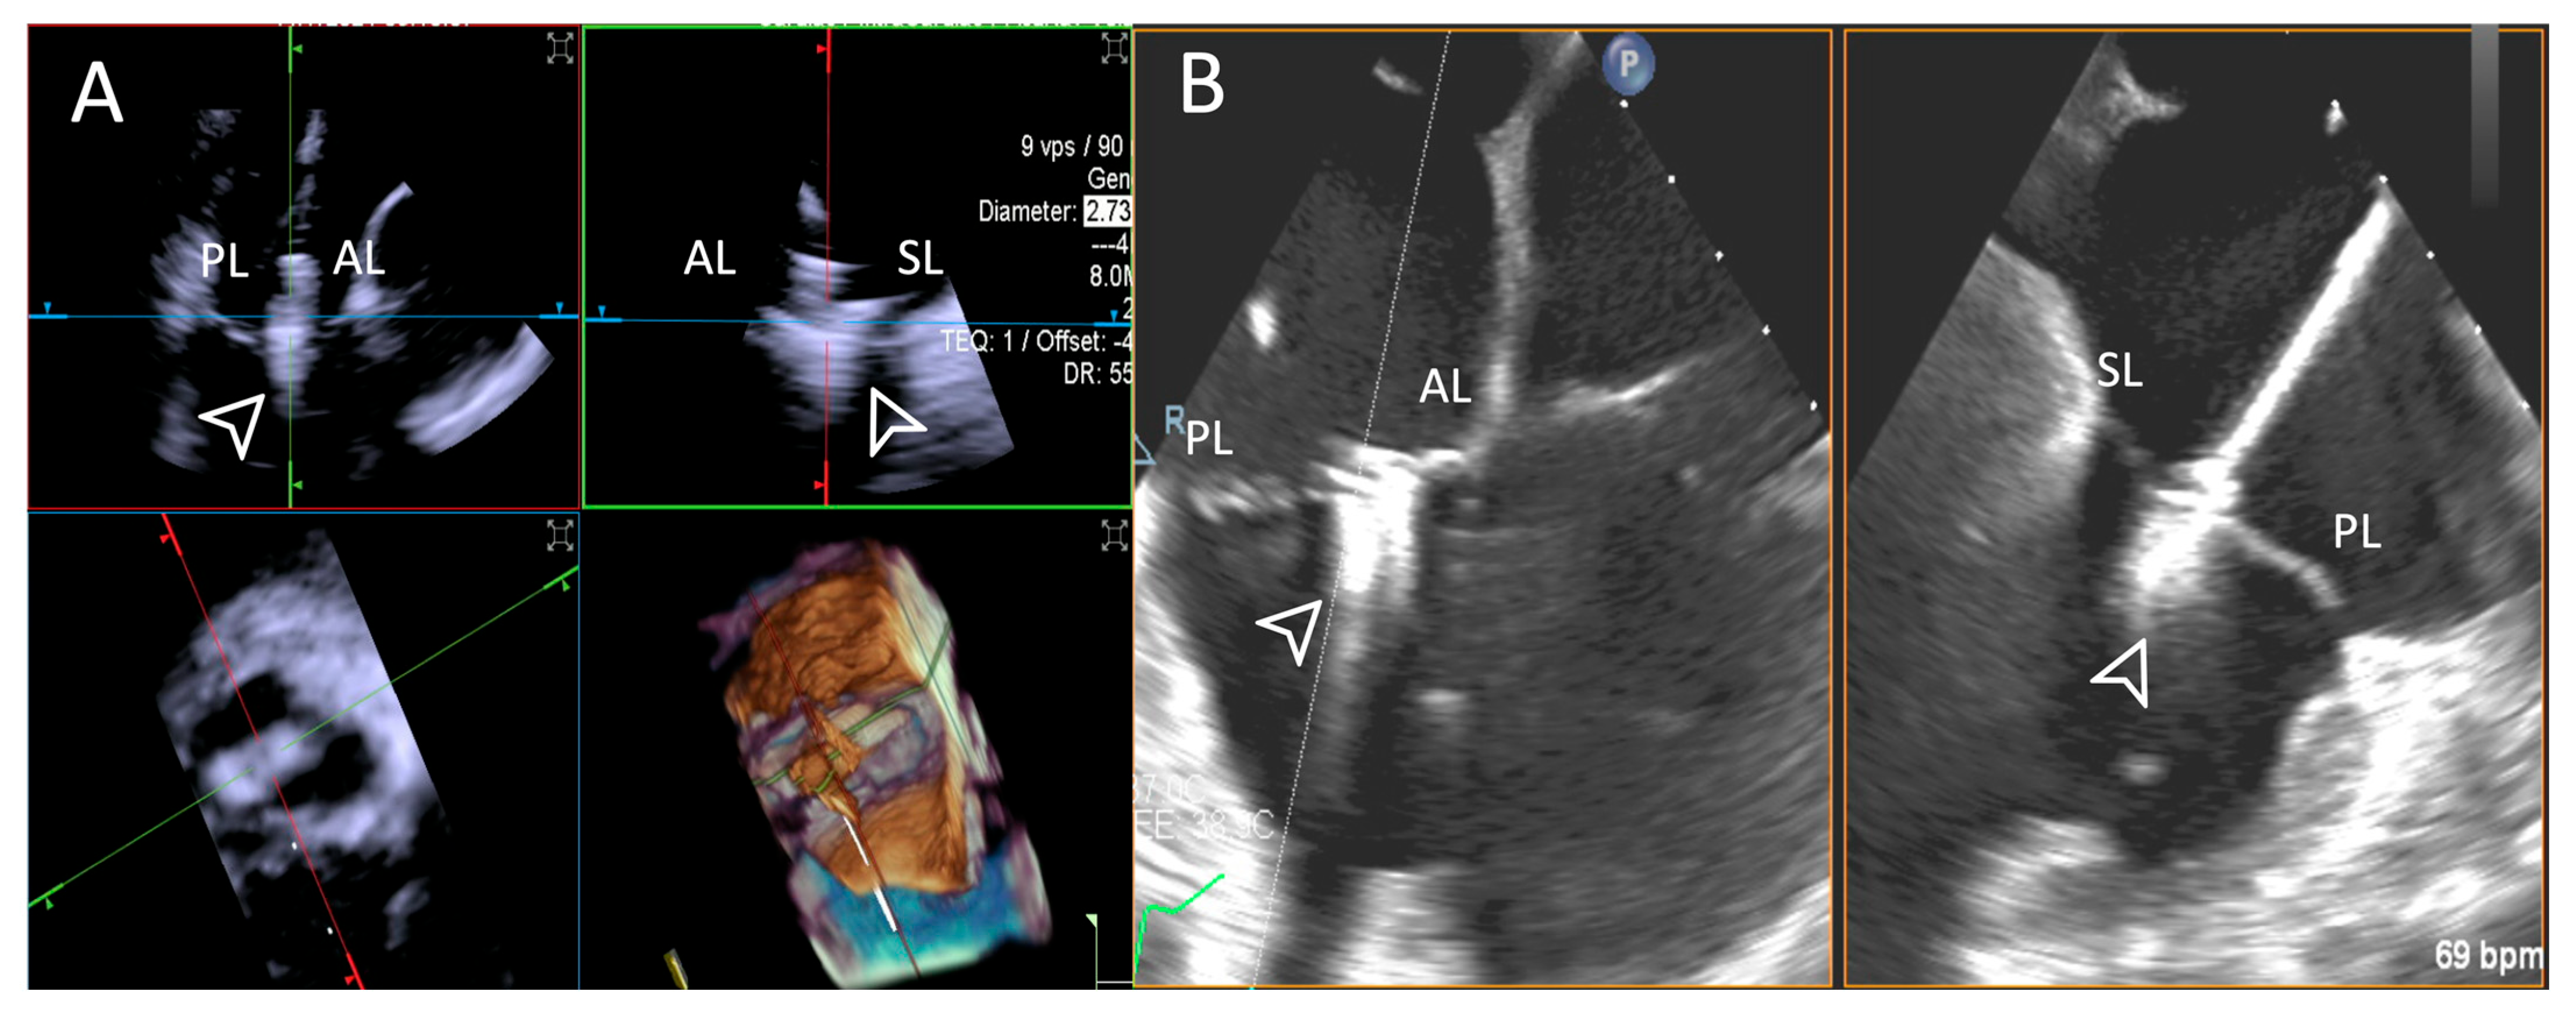

- Step number 1: assessment of tricuspid valve anatomy.

- Step number 2: identification of the target lesion.